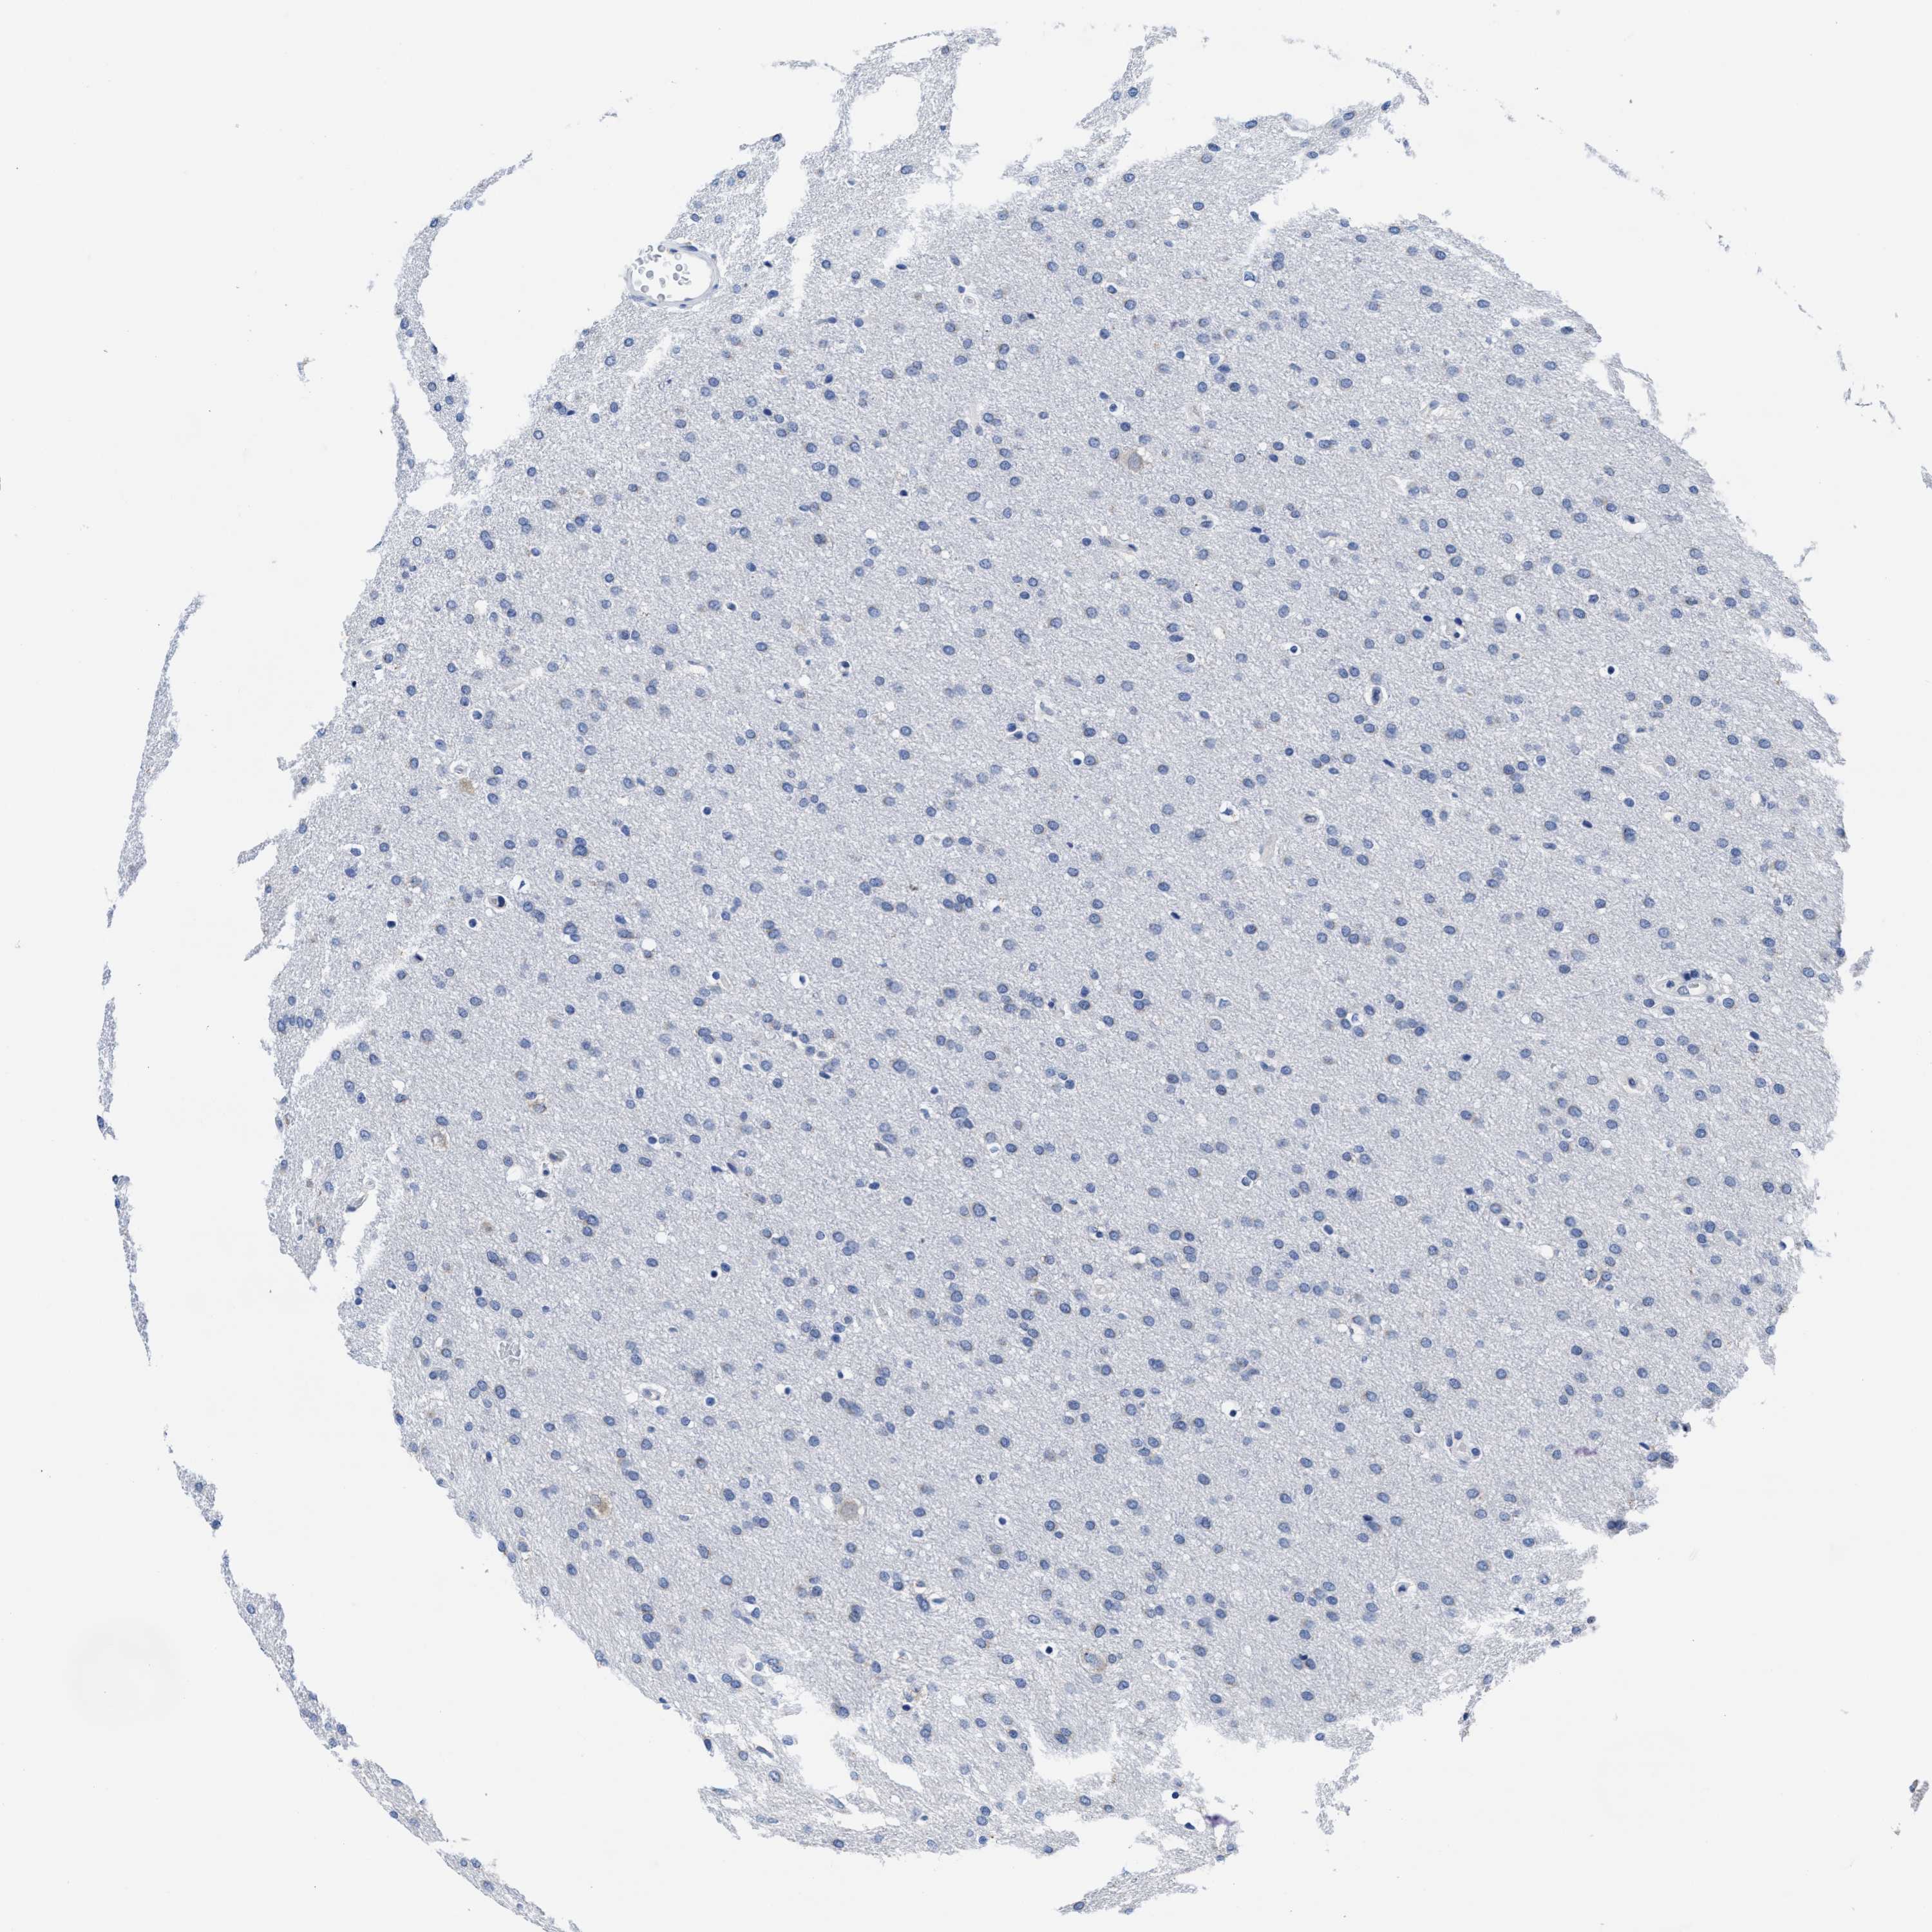

GLIOMA - Protein expressioni

A mouse-over function shows sample information and annotation data. Click on an image to view it in a full screen mode. Samples can be filtered based on level of antibody staining by selecting one or several of the following categories: high, medium, low and not detected. The assay and annotation is described here.

Note that samples used for immunohistochemistry by the Human Protein Atlas do not correspond to samples in the TCGA dataset.

Antibody stainingi

Antibody staining in the annotated cell types in the current human tissue is reported as not detected, low, medium, or high, based on conventional immunohistochemistry profiling in selected tissues. This score is based on the combination of the staining intensity and fraction of stained cells.

Each image is clickable and will lead to virtual microscopy that enables deeper exploration of all samples and also displays staining intensity scores, fraction scores and subcellular localization as well as patient and tissue information for each sample.

Antibody HPA018537

Antibody HPA018820

Staining

High

Medium

Low

Not detected

Intensity

Strong

Moderate

Weak

Negative

Quantity

>75%

75%-25%

<25%

None

Location

Nuclear

Cytoplasmic/membranous

Cytoplasmic/membranous,nuclear

Glioma, malignant, High grade

Glioma, malignant, Low grade